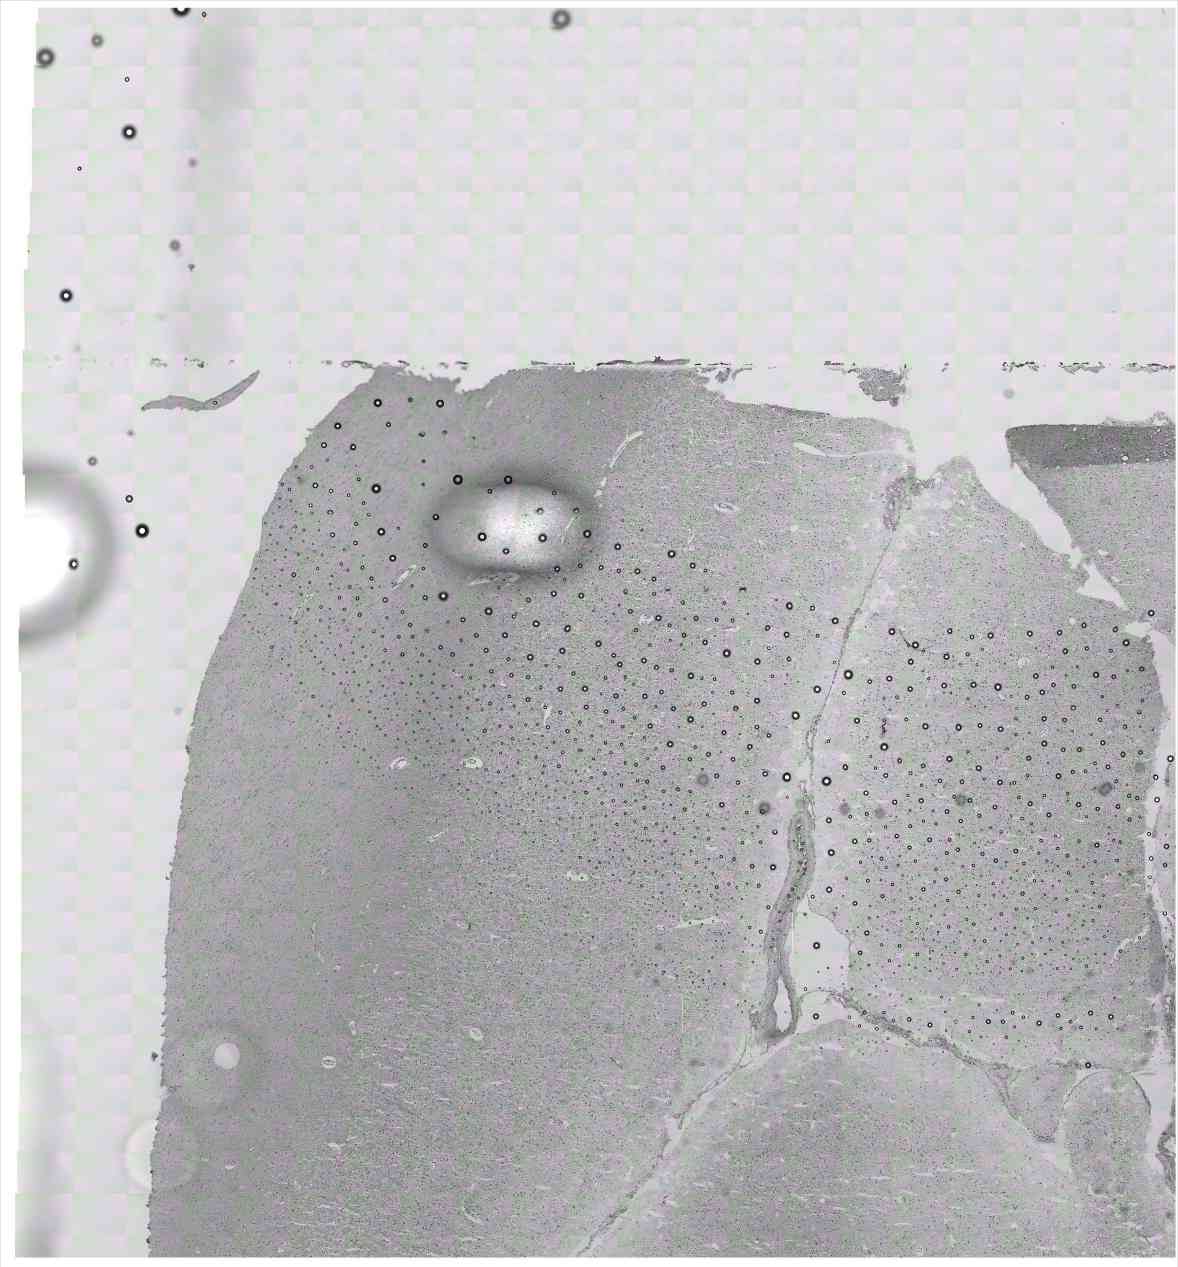

Chip 019 Well C1